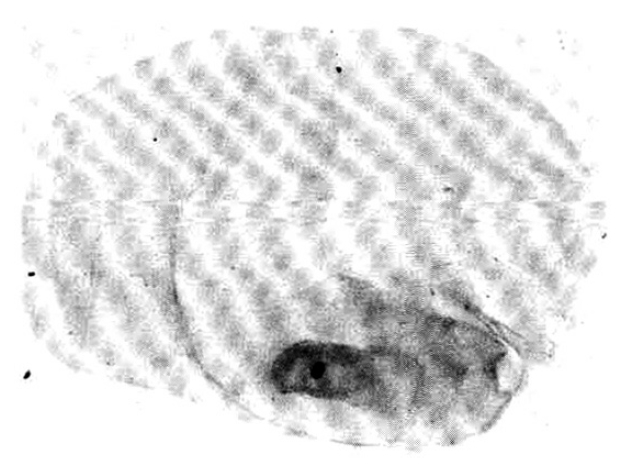

An X-ray film of the chest showed multiple nodular densities throughout both lower lung fields (Fig. 1). A computed tomographic scan of the brain and chest revealed multiple nodular and small calcified densities (Fig. 3, 4).

A biopsy of a subcutaneous nodule was done on the 4th hospital day, and upon microscopic examination, a bladder worm (Fig. 5)—its hooks (Fig. 6) and parenchymatous portion with spinal canal and separated bladder of the cysticercus (Fig. 7)—was observed. On the 12 th hospital day, the presence of cysticercus was confirmed by an open lung biopsy (Fig. 8).